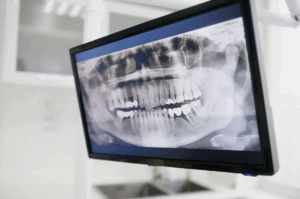

Una evaluación personalizada con radiografías y escáneres 3D permite determinar si el procedimiento inmediato es seguro.